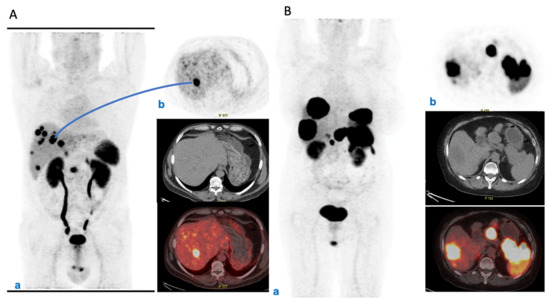

| 10. Evaluation of response (morphological vs. functional and clinical) after RLT | Assessment of tumor response after RLT should carefully consider both morphological and functional imaging. However, the timing of imaging should be correlated with characteristics of the individual tumor. |

| 11. Follow-up after RLT | Follow-up should be patient-tailored and include morphological (CT and/or MRI) and/or functional (PET/CT with radiolabeled somatostatin analogs and/or FDG) imaging and biomarkers, chosen based on the characteristics of the tumor. The timing should be modulated based on prognostic parameters, while strongly considering safety issues. It is suggested to intercalate morphological and functional imaging to reduce the patient’s irradiation dose given the very long follow-up. |